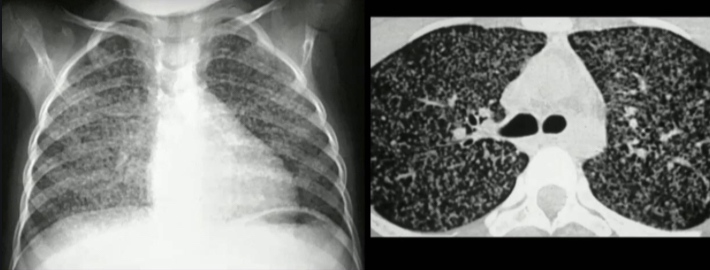

Como você interpreta esta imagem em um paciente pediátrico com suspeita de TB?

Rx de Tx com micronódulos pulmonares bilaterais, típicos de TB miliar